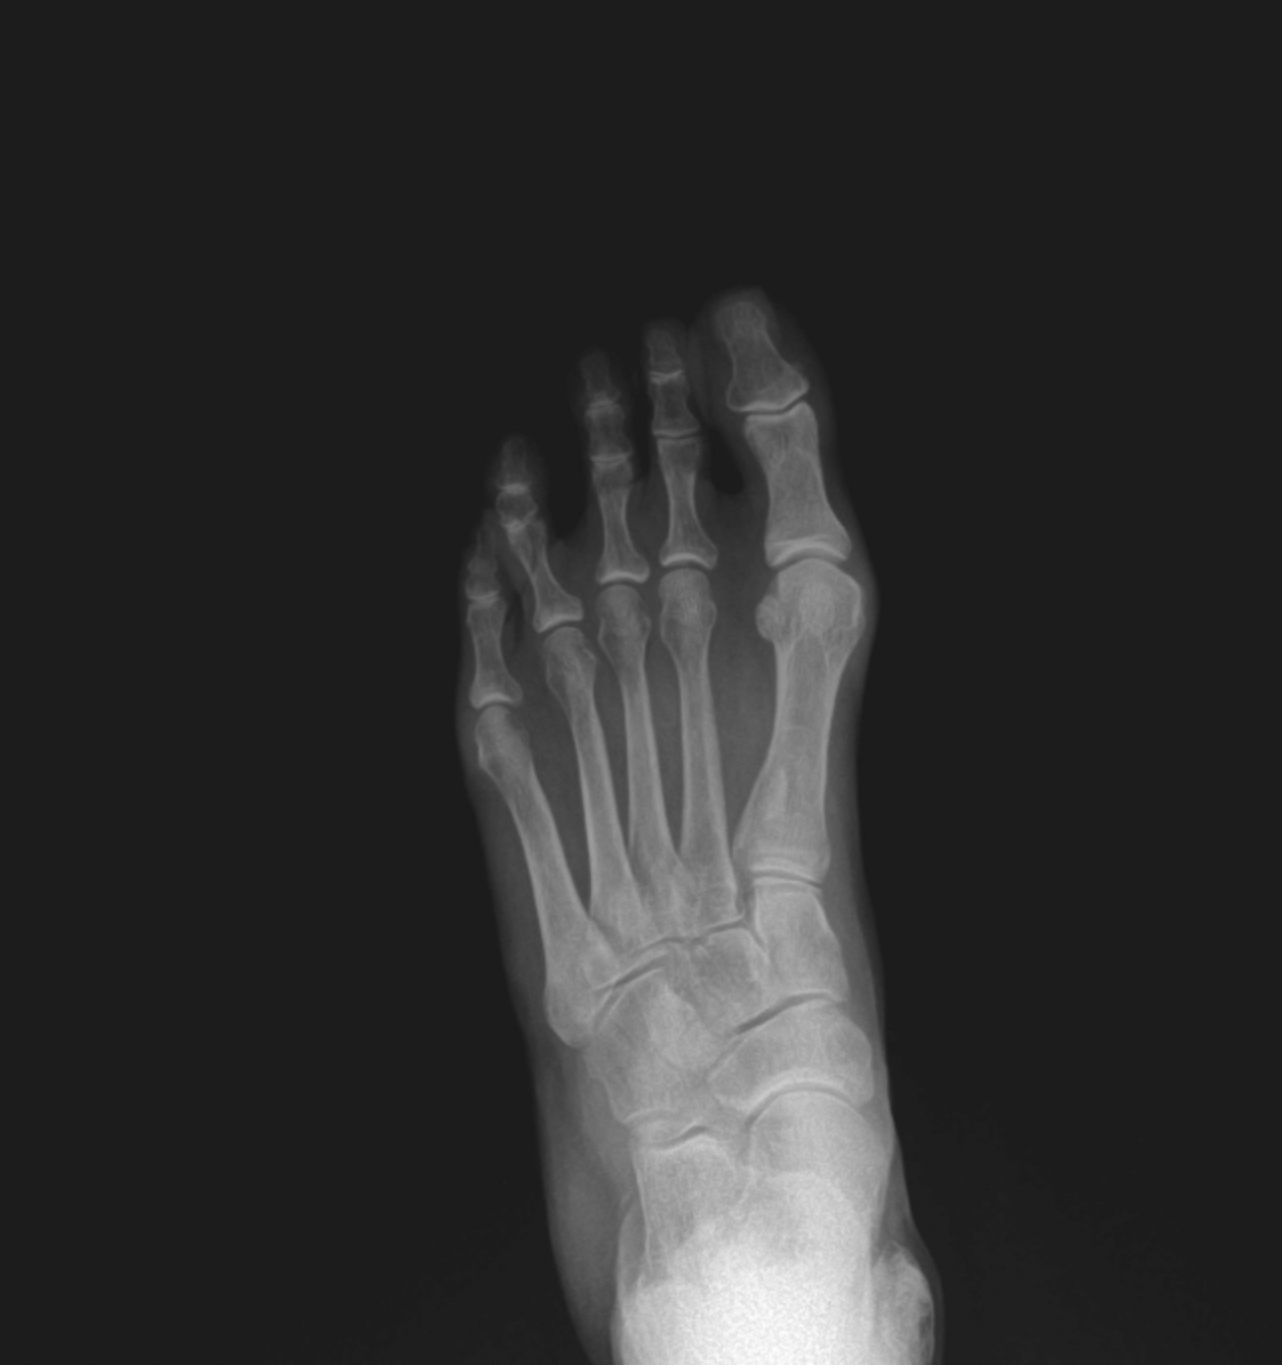

Arthritic flatfoot

Pre-op XR Images